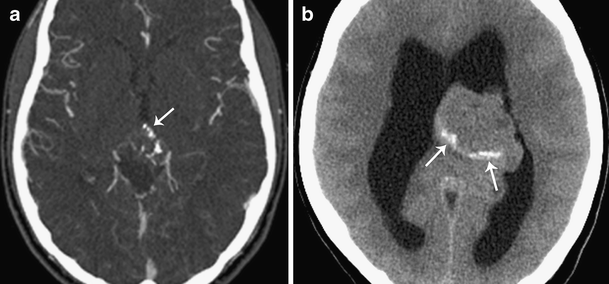

Occasionally, tumors or cysts can arise from this gland which may require. It can be benign (noncancerous) or malignant (cancerous). In their 1954 pineal tumor study, ringertz and colleagues defined the pineal region as being bound by the splenium of the corpus callosum and tela choroidea dorsally, the quadrigeminal plate and midbrain tectum ventrally, the posterior aspect of the third ventricle rostrally, and the cerebellar vermis caudally.